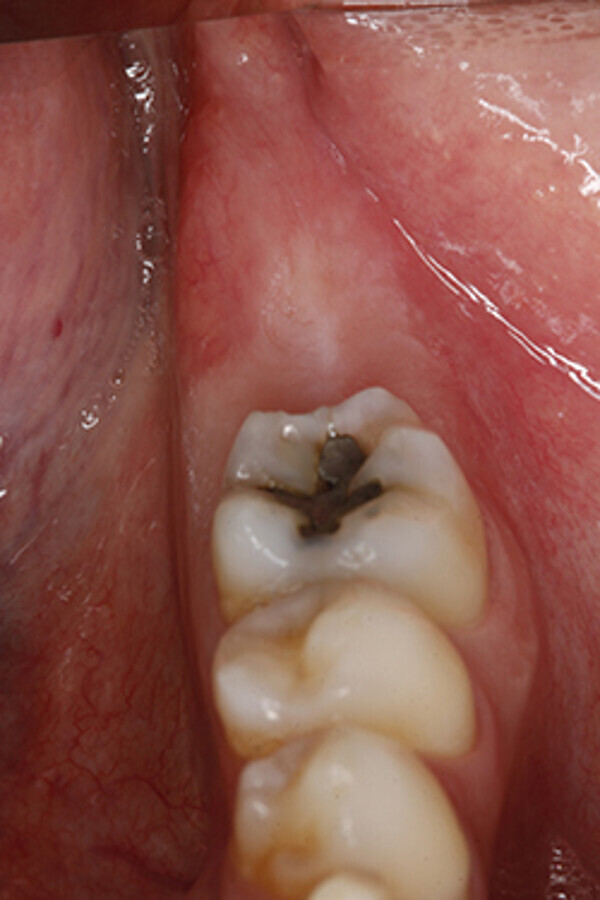

Tras un periodo de osteointegración de tres meses se realizó una cirugía de acceso para colocar el pilar de cicatrización de implante 3.7 y posterior registro con escáner intraoral (3shape Trios®, Copenaghen, Denmark) (Fig. 13), para la confección de la prótesis atornillada definitiva (Fig. 14)

Figura 13. Fase protésica. A) A las 12 semanas de la cirugía de implantes, se realizó una segunda cirugía para colocar el pilar de cicatrización a nivel de 3.7. B) Pilar de cicatrización atornillado. C) A los 15 días se procede tomar registros de impresión con un escáner intraoral. Nótese los scan-bodies en posición.

Figura 14. Fase protésica. Imágenes intraorales. A) Vista oclusal de la salud de los tejidos periimplantarios el día de colocación de la prótesis. B) Vista oclusal de la prótesis ceramo-metálica atornillada. C) Vista lateral de la prótesis definitiva, nótese el esquema oclusal de la restauración.